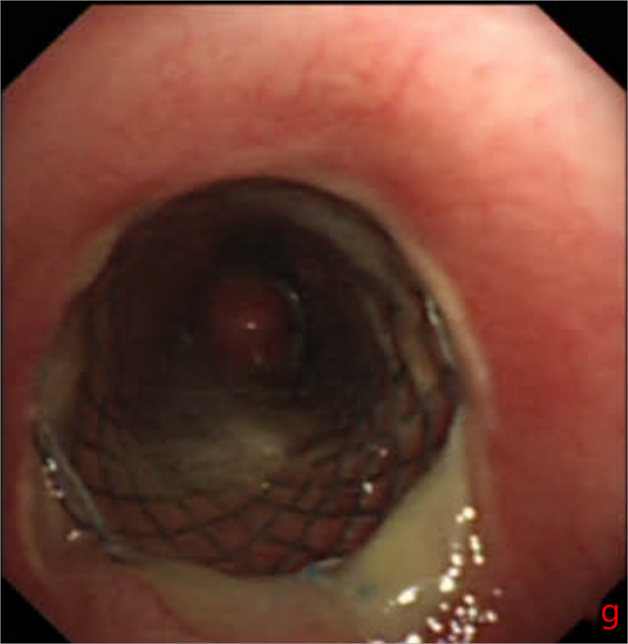

2025年10月10日,手术在全麻下顺利开展。医护团队通过支气管镜的精准引导,将支架成功植入患者气管狭窄部位,整个过程平稳有序。术后奇迹很快显现:W先生的呼吸困难症状当场明显缓解,复查胸片提示气道下段通畅度显著改善,没过多久便能正常进行日常活动。短暂恢复后,他顺利返回继续接受胸部肿瘤放疗,整个放疗过程进展顺利,胸部肿瘤明显缩小。

同年12月19日,W先生再次来到温岭市第一人民医院,在接受肿瘤相关治疗的同时,医护团队为他实施了支架取出手术。术后检查显示,他的气管保持通畅,呼吸顺畅,目前生活状态良好,已恢复正常生活节奏。

“经支气管镜气管支架植入术,是解决中心气道狭窄的关键微创技术。”李相国介绍,对于肿瘤进展导致气道梗阻的患者,这项技术能迅速解除窒息风险,改善通气功能,更重要的是能为后续的肿瘤局部治疗(如放疗)创造安全的治疗窗口,是衔接多学科综合治疗的重要桥梁。其最大优势在于“微创”——无需开胸,让患者在短时间内恢复呼吸通畅。